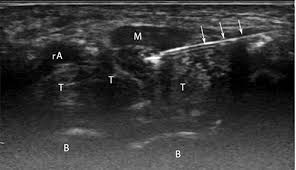

Hand And Arm Pain A Pictorial Guide To Injections Mdedge Family Medicine